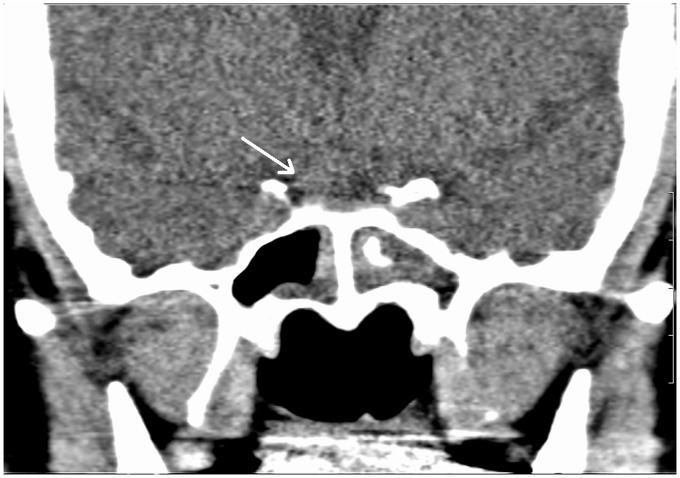

一例孤立的蝶骨真菌鼻窦炎在一个老年糖尿病患者被描述。偶然发现位于鞍区共存的肿块病变。这两个实体的重合代表了潜在的手术灾难,可能导致真菌感染的直接颅内扩散。

A case of isolated sphenoid fungal sinusitis in an elderly diabetic patient is described. A coexisting mass lesion located in the sellar region was detected incidentally. Coincidence of these two entities represents a potential surgical disaster which may result in direct intracranial spread of fungal infection.